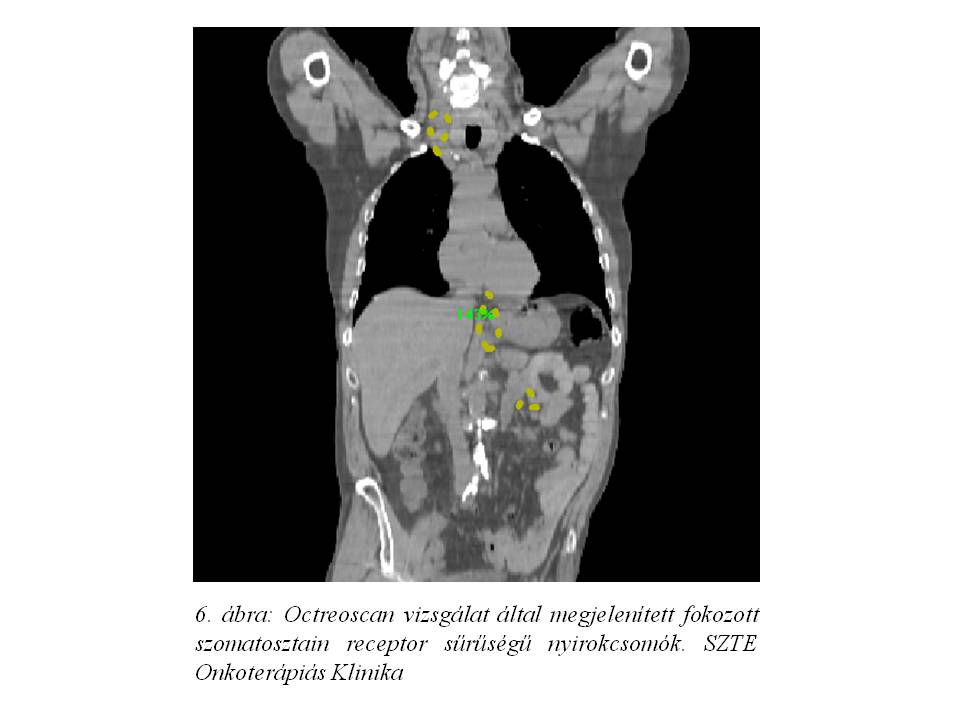

Az esetet ismételten megvitattuk intézetünk onko-team megbeszélésén, mely octreoscan vizsgálatot javasolt.

A szomatosztatin receptor szcintigráfiás vizsgálat primer eltérést szintén nem tudott elkülöníteni, de a felvételeket összevetve az FDG PET/CT vizsgálat során leírt nyirokcsomókkal, túlnyomórészt fokozott szomatosztatin receptor sűrűséggel rendelkező elváltozásokat írt le (6. ábra).

Ez alapján indult el a beteg kezelése somatostatin receptor analóggal.